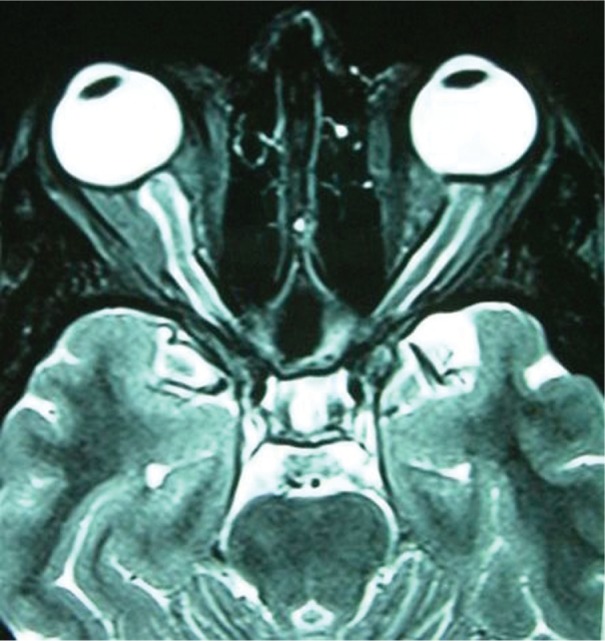

A 36-year-old female was admitted (to the Department of Neurology, Hacettepe University Medical Faculty, Department of Neurology, Neuro-ophthalmology Unit, Ankara, Turkey) with the complaints of headache and severe bilateral visual loss that had progressed rapidly in 3 months. She was found to have papilledema on examination and had been treated with acetazolamide 250 mg qid for 8 weeks elsewhere. Idiopathic intracranial hypertension (IIH) was considered in diagnosis although opening pressure was recorded normal in the lumbar puncture (LP). On our examination her visual acuity (VA) was light perception OD and 20/100 OS. There was a right afferent pupillary defect. Fundoscopy revealed pale optic nerve head with blurred margins on the right and chronic disc edema on the left. She was not able to identify any of the Ishihara color plates OU. LP was performed with an opening pressure of 22 cm of H2O. CSF analysis showed protein level of 40 mg/dL and no cells. MRI studies revealed a fluid-filled dilated optic nerve sheath surrounding the optic nerves (Figure 1). There was no evidence of a space-occupying lesion. Her left VA decreased to counting fingers in a week. The CSF pressure at the repeat LP was significantly low which could not be recorded. Dural ectasia of the optic nerve is considered in diagnosis. Due to progressive dysfunction of the optic nerve despite treatment with carbonic anhydrase inhibitors, optic nerve sheath decompression via medial transconjunctival approach was performed bilaterally by an ophthalmic surgeon (HK). The distal part of the orbital portion of the optic nerve was found to be significantly enlarged and had a bulb-like appearance. The dura was streched but otherwise looked normal. Overlying dural vessels were also enlarged and tortuous. Three parallel longitudinal incisions, each measuring 2 to 2.5 mm in length, were made into the dura along the enlarged optic nerve. Large amount of clear fluid rapidly egressed with pressure following the first incision. The optic nerves deflated within seconds while cerebrospinal fluid continued to ooze for a while. No intraoperative complications were observed. The left optic disc edema resolved within one week and the patient remained stable over the next 3 months with the same visual acuity.

Figure 1.

Fluid-filled dilated sheath surrounds normal optic nerves on T2-weighted axial MRI.